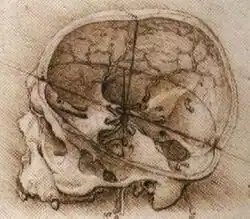

![]() Human brain and skull | |